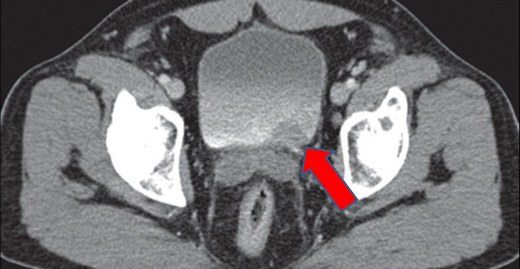

Mesane kanserlerinin çoğu mesanenin iç yüzeyindeki epitel tabakasından başlar ve tümör büyüdükçe mesane duvarlarındaki kaslara yayılır. Kasa invaze olmayan (yüzeyel) mesane kanserlerinin diğer mesane kanserlerine göre oranı % 75, kasa invaze olan mesane kanserlerinin oranı % 20, metastatik mesane kanserlerinin oranı ise % 5 olarak belirtebiliriz.

Mesane kanserinin tedavisinde cerrahi tedavi yöntemleri yaygın

Mesane kanseri vakalarının % 90’ından fazlasında cerrahi yöntem ya tek başına ya da başka tedavi yöntemleriyle bir arada kullanılıyor2.Daha ileri safhadaki kanserlerde sistektomi yöntemi ile  mesanenin tamamen alınması da gerekebiliyor .